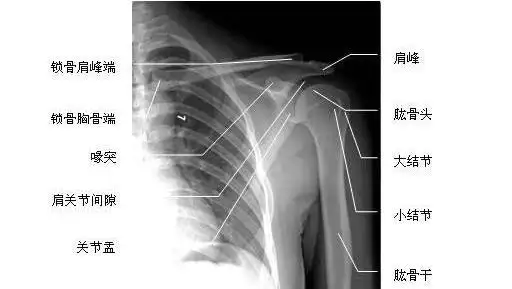

肩关节正位-x线图